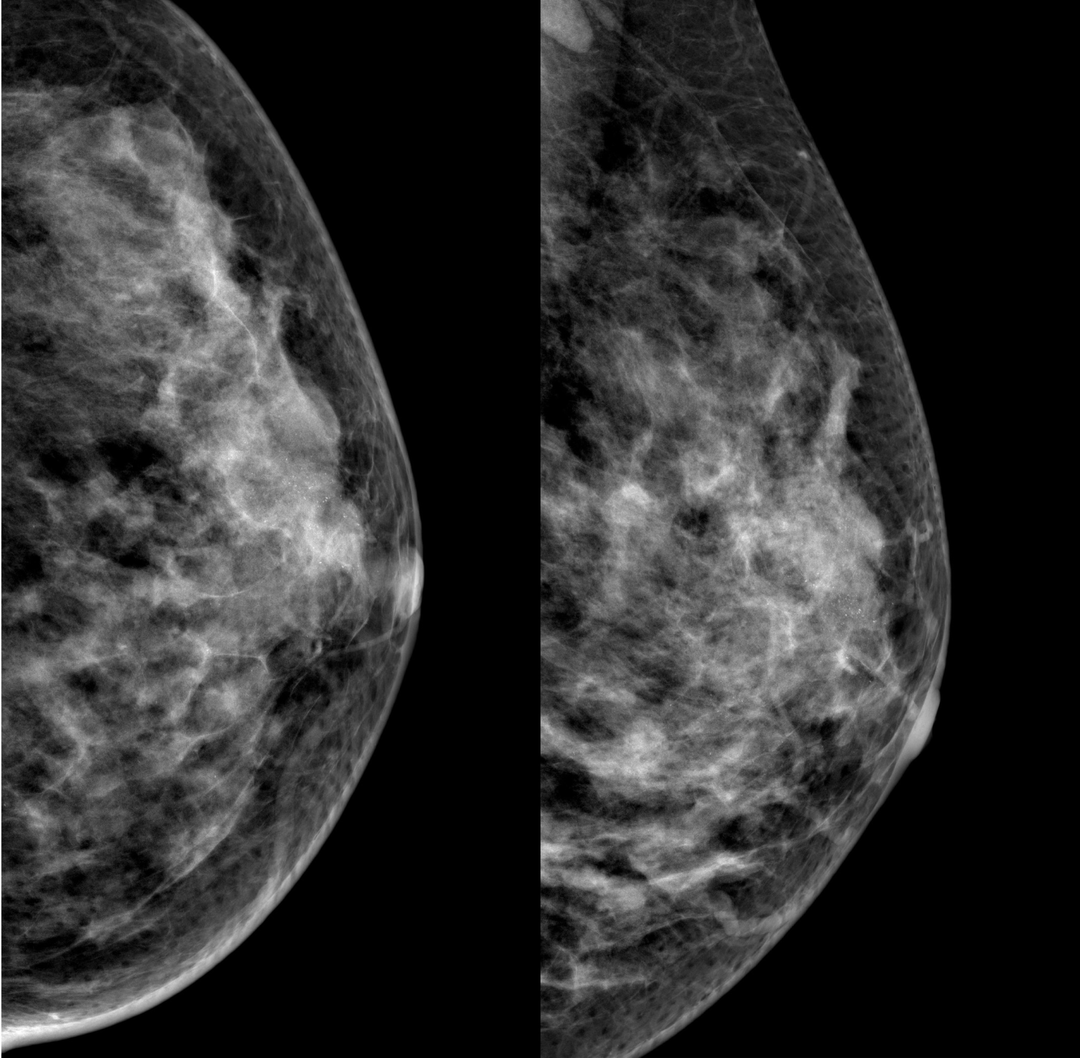

病例1:左乳簇状分布钙化灶,左腋下淋巴结显示

数字化摄影是什么检查好消息!助力乳腺癌早期诊断 青田人民医院数字化乳腺X线机正式投入使用_https://www.jmylbn.com_新闻资讯_第9张

数字化摄影是什么检查好消息!助力乳腺癌早期诊断 青田人民医院数字化乳腺X线机正式投入使用_https://www.jmylbn.com_新闻资讯_第13张